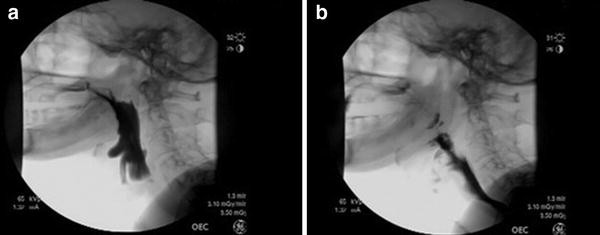

Dysphagia Following Anterior Cervical Surgery

Lecture Dysphagia Following Acdf Surgery